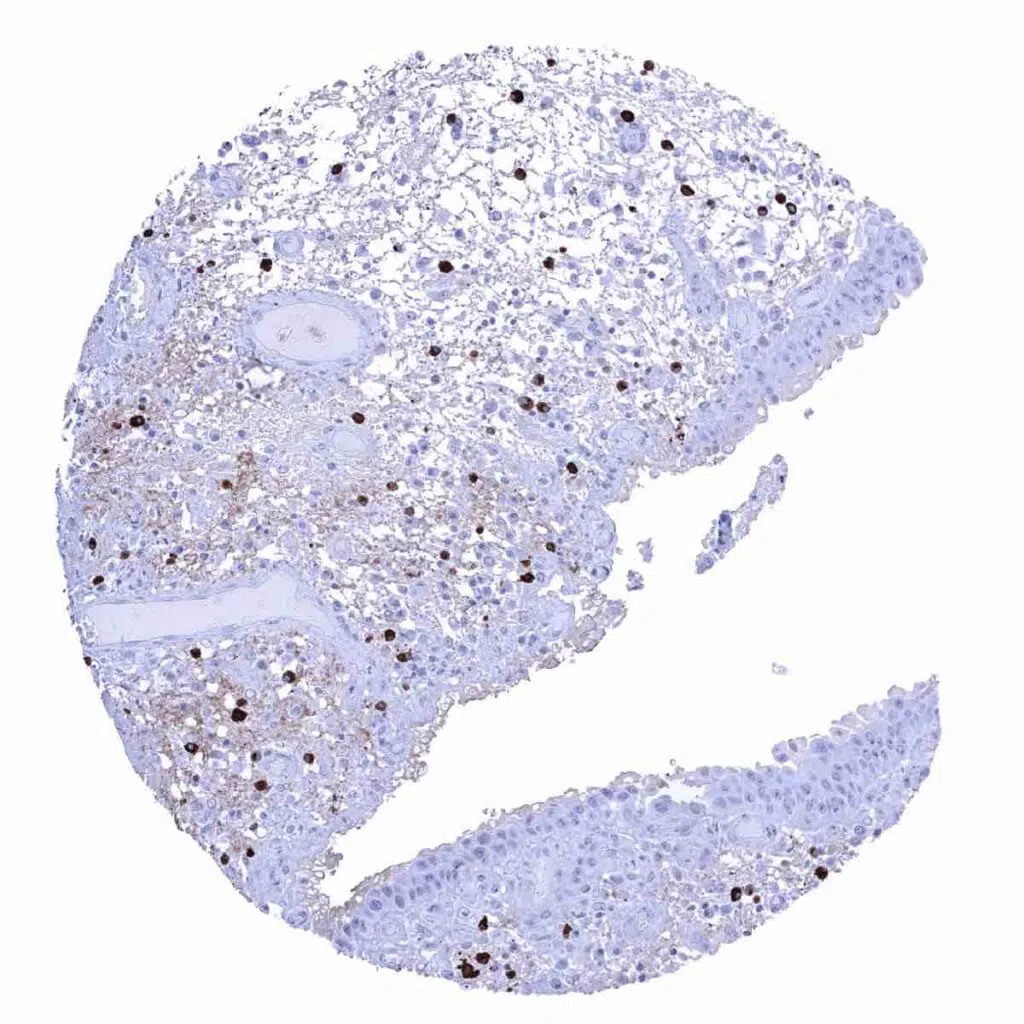

Bone marrow – Rabbit anti-human IgA positive plasma cells are rather rare.